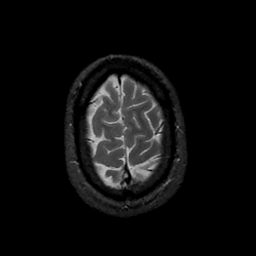

MR Study #11, May 5, 1991 -- Slice #44

[Home][Help][Clinical][Tour 1][Tour 2] Slice 44